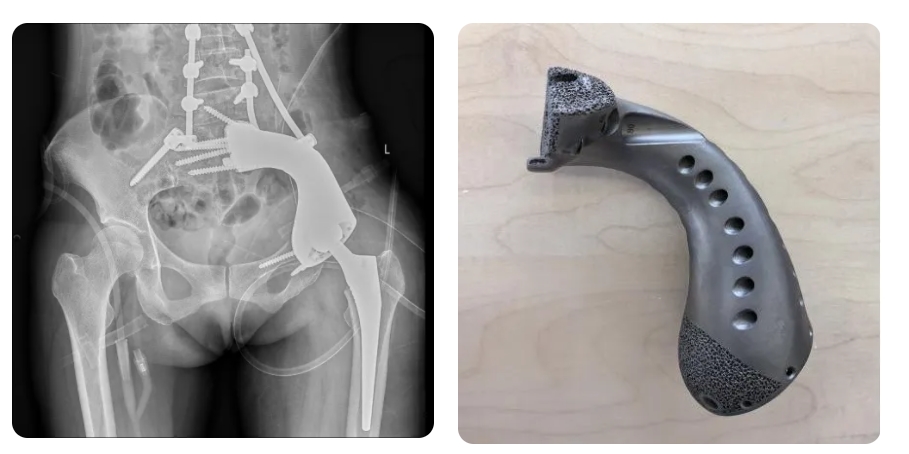

面对这一复杂病情,骨科肿瘤团队进行了综合评估,决定为患者实施左骨盆肿瘤 + 左侧骶骨肿瘤瘤体完整切除 + 3D 打印肿瘤假体置换手术。3D 打印肿瘤假体可量体裁衣,个体化重建肿瘤切除后的骨缺损,其微孔结构能实现假体与自体骨骨性愈合,提高长期稳定性,延长使用时间,这样不仅为患者成功保肢,还最大可能地保留肢体功能。

此次手术过程复杂,术前需评估患者身体机能及肿瘤,包括切除范围、重建方式、手术体位、术中出血控制等,手术通常需术中变换 2 - 3 个体位,手术时间 6 - 8 小时左右。骨肿瘤团队克服重重困难,历经7小时,成功完成肿瘤瘤体完整切除,并植入 3D 打印肿瘤假体,达到预期效果。